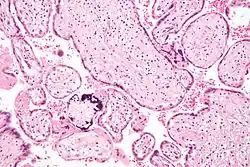

Micrograph of cytomegalovirus (CMV) infection of the placenta (CMV placentitis), a vertically transmitted infection: The characteristic large nucleus of a CMV-infected cell is seen off-centre at the bottom right of the image, H&E stain.

CMV placentitis